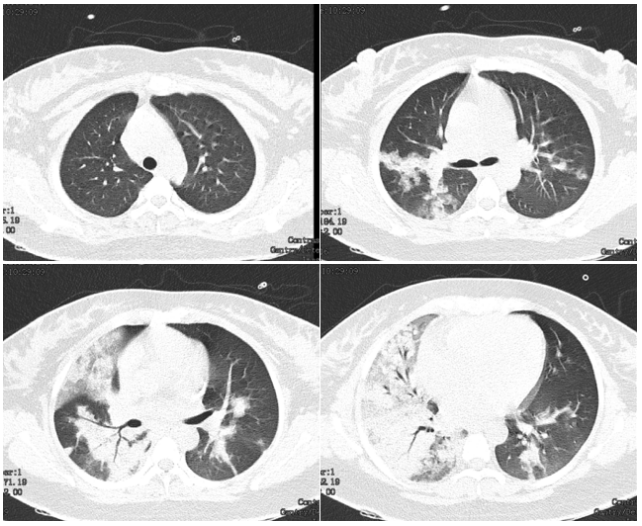

2、临床表现不同:新型冠状病毒肺炎患者常以发热、干咳、乏力为主,部分患者快速进展为呼吸困难、低氧血症,甚至急性呼吸窘迫综合征;部分感染者可能无症状,但仍具传染性。普通肺炎的症状多表现为发热、咳嗽、咳痰,胸痛较常见,呼吸困难通常与病情严重程度相关,无症状感染者极少见。

病因不同普通感冒由多种病毒引起,包括鼻病毒、冠状病毒(非新冠类型)、副流感病毒等,主要侵犯上呼吸道。而冠状病毒发烧特指由新型冠状病毒等冠状病毒引发的感染,常导致肺部病变,属于下呼吸道感染范畴。